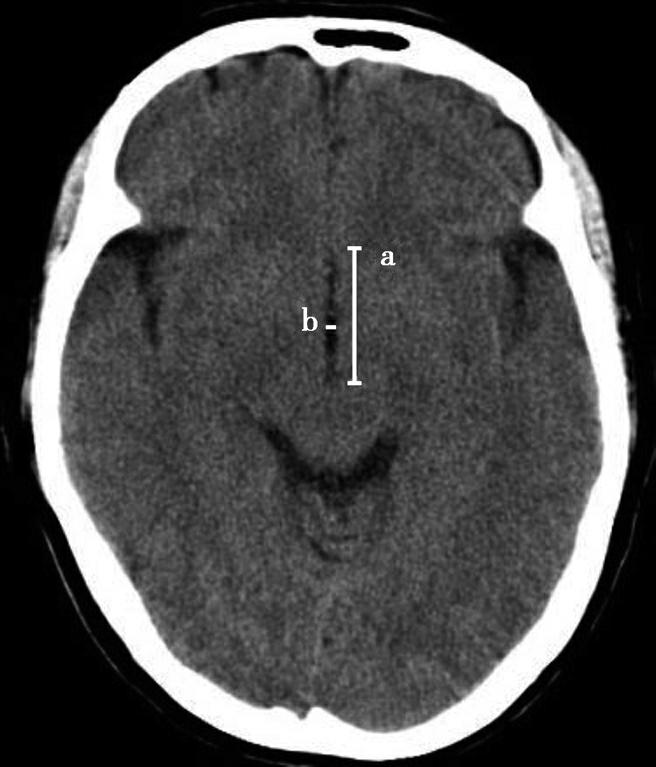

Alberta卒中项目早期CT评分(Alberta stroke program early CT score,ASPECTS)是一种评价急性缺血性卒中患者大脑中动脉供血区早期缺血性改变的简单、可靠、系统化的方法,是常用的脑卒中评定量表之一,可对缺血性病变快速进行半定量评价,有助于判定溶栓效果和远期预后。该评分主要基于CT平扫,具体分区如下(图1-2-76)所示,即选取大脑中动脉供血区2个层面。分区后共10个区域,每个区域记1分。评分时任何区域只要有低密度灶,则扣除该区域得分。正常脑ASPECTS评分为满分(10分),若MCA供血区广泛梗死累及全部区域时,则ASPECTS评分为0分。

图1-2-76 ASPECTS评分脑组织分区

A.在基底节层面(即丘脑和纹状体平面),分为各级分支M 1 、M 2 、M 3 、岛叶(缩写I)、豆状核(缩写L)、尾状核(缩写C)和内囊(缩写IC)后肢等7个区域;B.在基底节以上层面(基底节层面上2cm),包括M 4 、M 5 和M 6 。